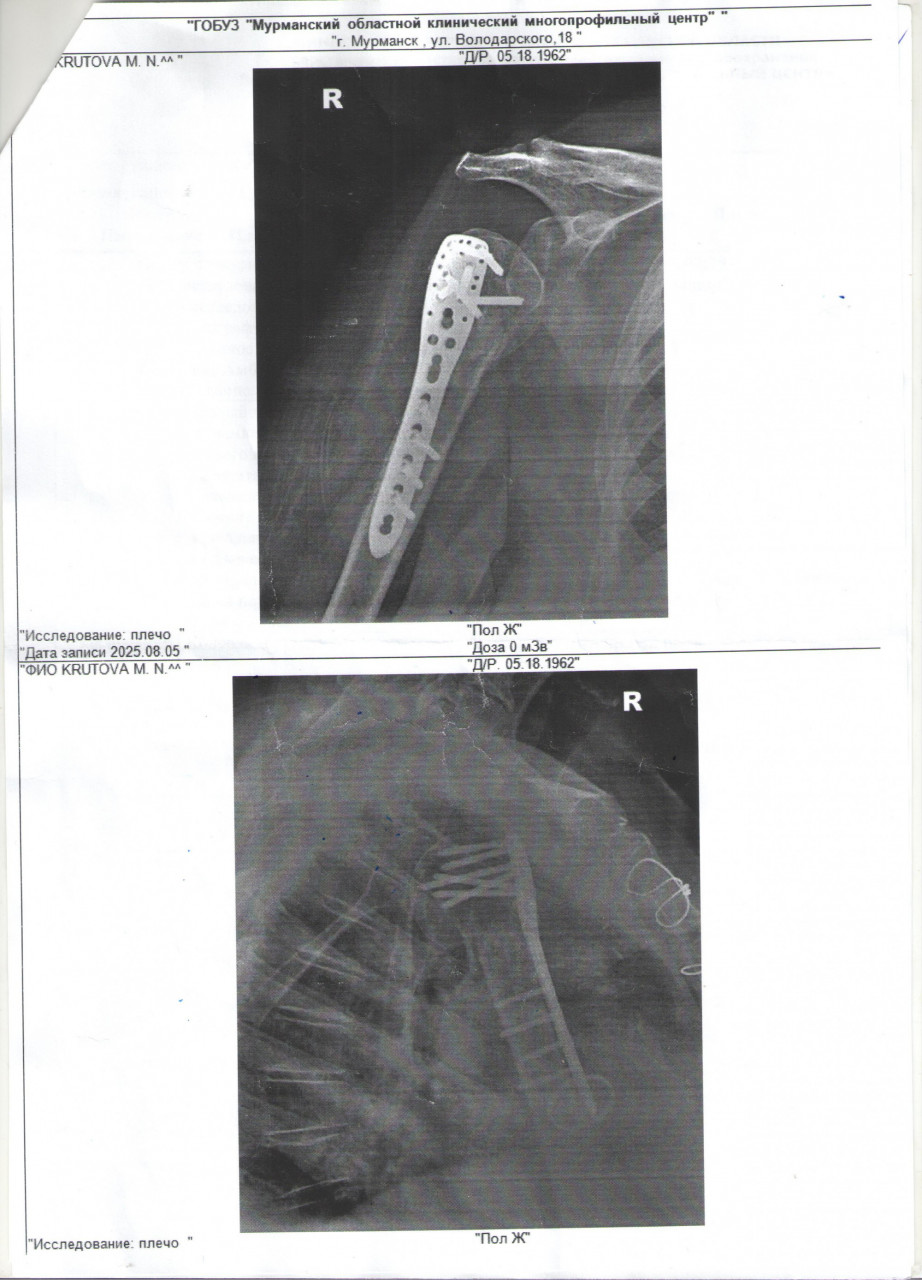

Послеоперационный свищ. Перелом плечевой кости с околками и отрыв большой головки. операция, поставлена пластина. после операции -глубокая инфекция и свищ. Флора чистая. Предлагают оперативное лечение. Другой травматолог предлагает восстановить руку и только потом решать вопрос со свищем, тк рука может не восстановиться.

Здравствуйте. В вашем случае сформировался хронический послеоперационный свищ, что говорит о неполном заживлении тканей вокруг пластины. По снимкам видна металлоконструкция, а при наличии свища консервативные методы (промывания, антибиотики, физиотерапия) редко дают стойкий результат и радикально решить проблему обычно можно только хирургически (иссечение свища, санация и при необходимости удаление пластины). То, что в посеве не выявлено патогенной флоры, не исключает хронической инфекции, так как бактерии могут находиться в биоплёнке на металлоконструкции и не определяться в обычных анализах. Поэтому стандартный подход это оперативное лечение. Вопрос о том проводить ли его сразу или сначала дождаться восстановления функции руки решается индивидуально. Если свищ не даёт выраженных симптомов (гной, температура, прогрессирующее воспаление), врачи иногда откладывают операцию до этапа когда рука окрепнет.

Здравствуйте.  Свищ после операции с металлоконструкцией чаще всего связан с хроническим воспалением вокруг пластины. Если флора в анализе не выявлена это не значит, что инфекции нет т.к микробы могут быть в биоплёнке на металле. Консервативное лечение (перевязки, промывания, антибиотики) может временно сдерживать процесс, но радикально устранить свищ обычно может только хирургическое вмешательство. С учётом вашего возраста, диабета и протеза клапана решение об операции принимается осторожно и иногда целесообразно сначала укрепить руку и общее состояние, а вопрос иссечения свища решать позже. В любом случае нужно наблюдение у травматолога, контроль анализов крови и регулярная обработка свища, чтобы не допустить обострения.